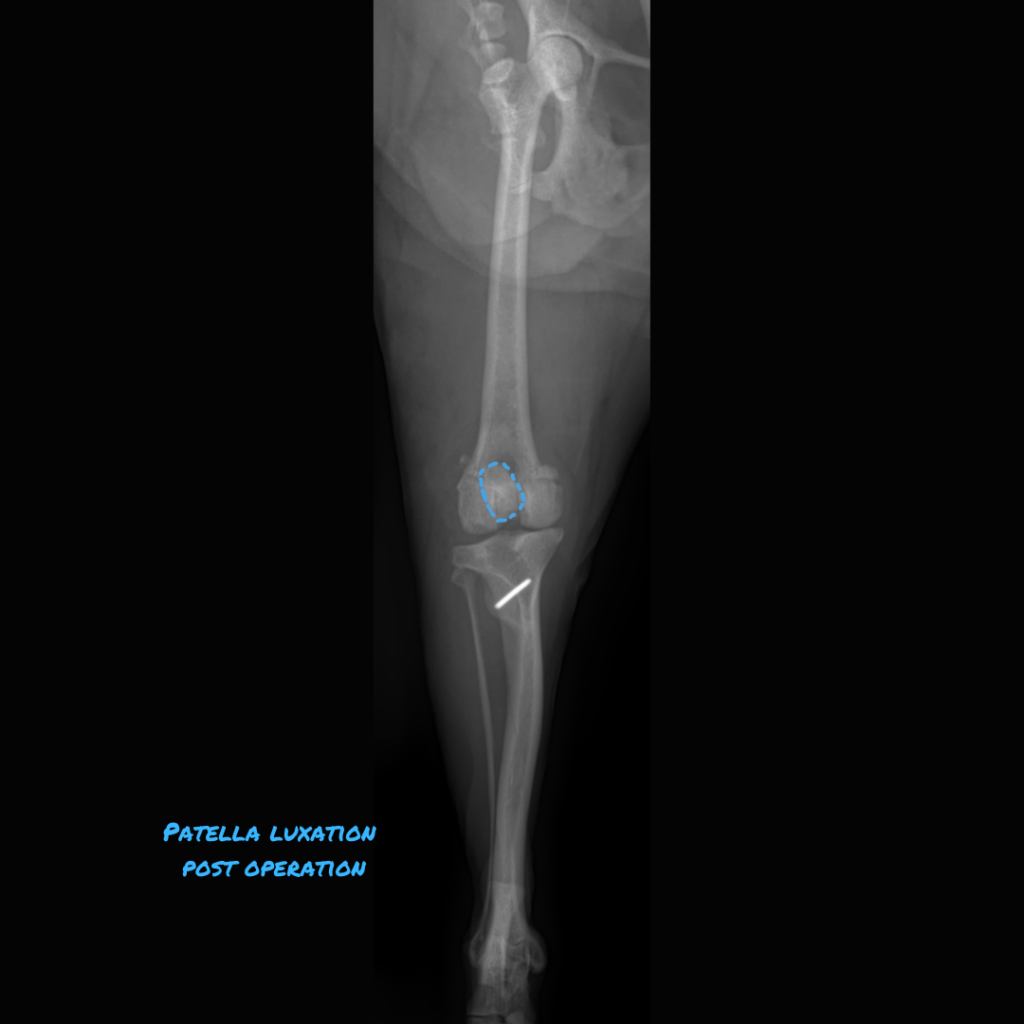

[Pic 1: The patella is highlighted with an orange dotted line and is luxated medially]

[Pic 2: The tibial tuberosity was shifted laterally and the groove was made deeper, so the patella is now sitting in its proper spot in the middle. (blue dotted line)